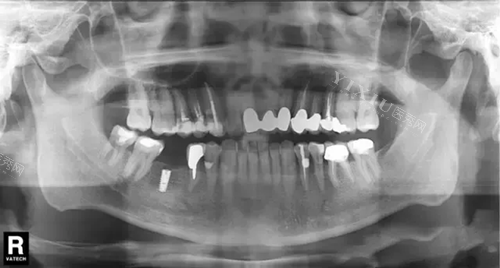

德国Ankylos种植体X光片.webp